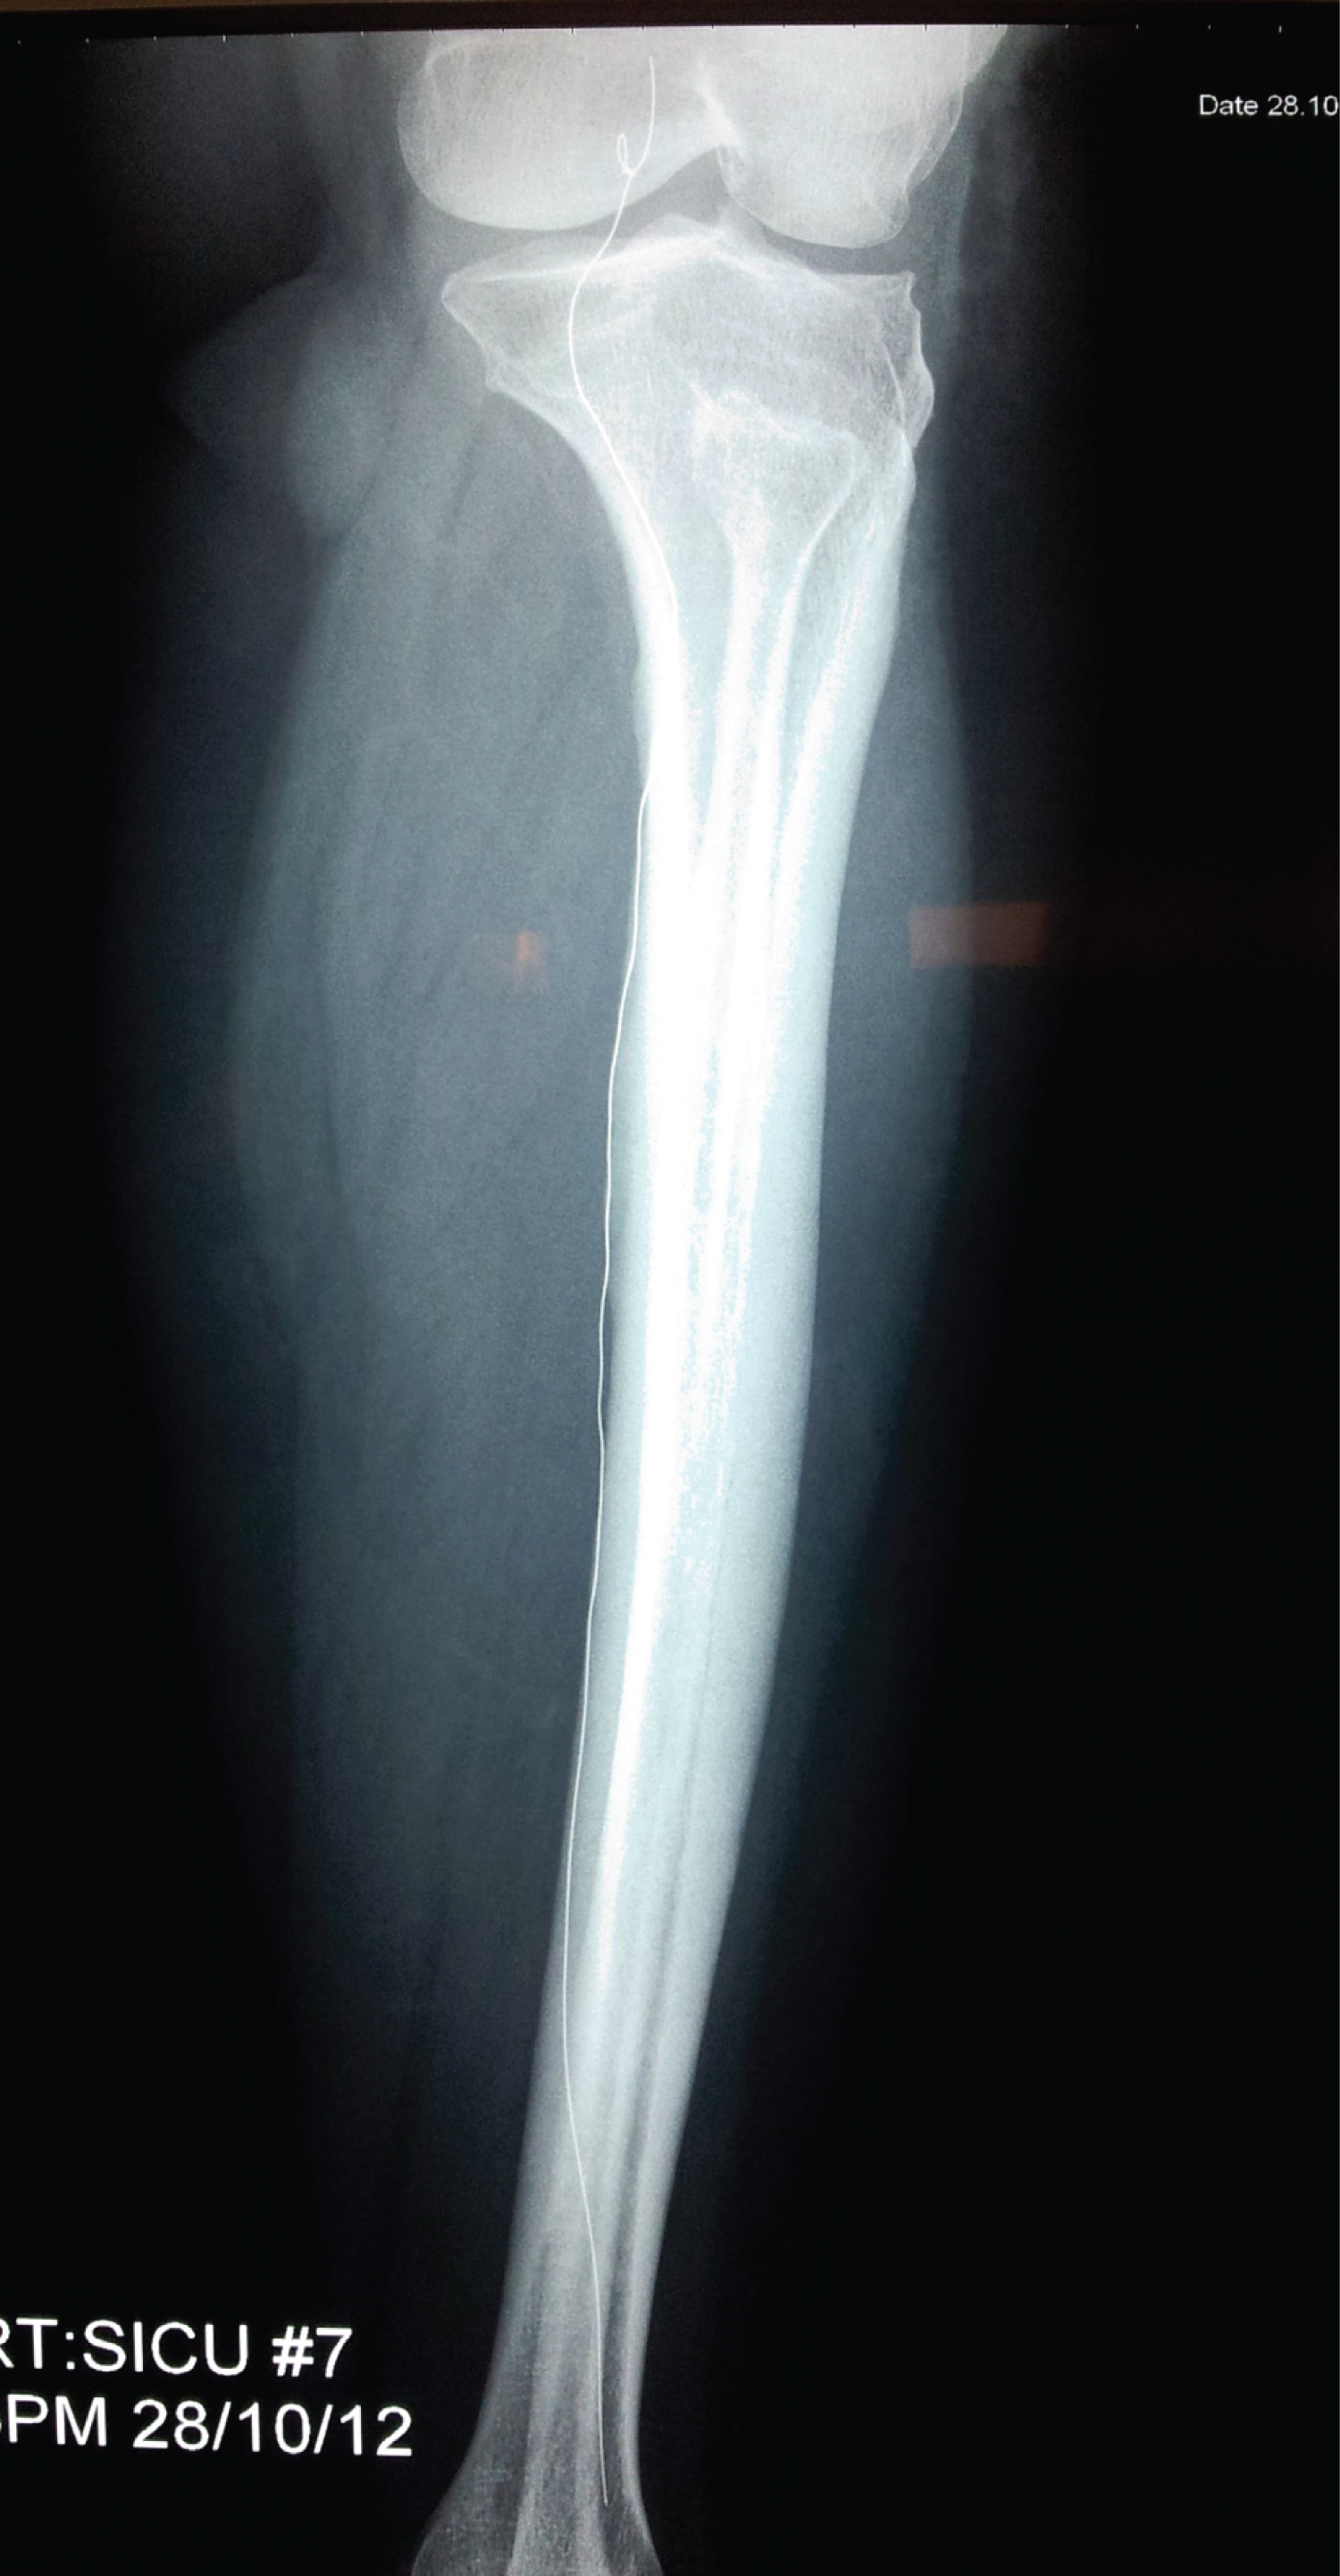

On day 2, extremity X-ray (Figure 1) detected the lost coil in the left popliteal artery. There were no circulation defects in the left lower limb. On day 3 the patient was taken for cerebral angiography and with the help of micro-balloon catheter the giant cerebral aneurysm was successfully obliterated with multiple coils (Figure 2).

Figure 1: Misplaced coil detected in the left popliteal artery on X-Ray. View Figure 1